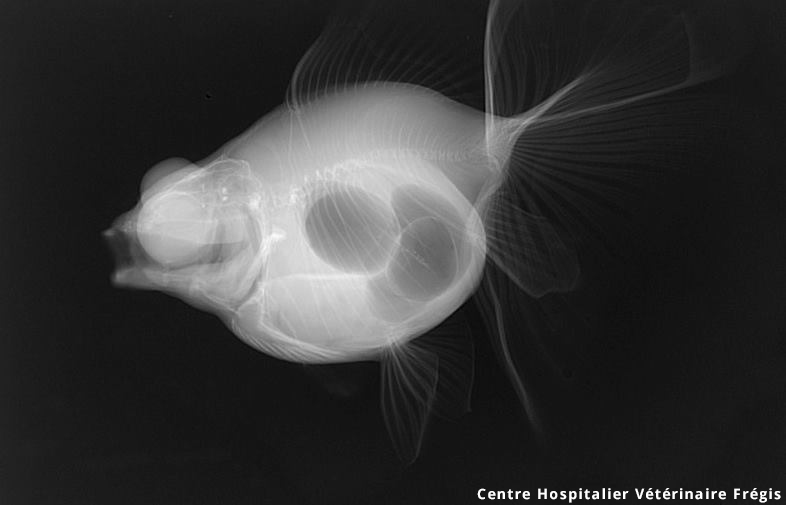

La maladie de la vessie natatoire chez les poissons rouges est lun des problèmes les plus courants rencontrez principalement chez les poissons rouges au corps ramassé.

Description du problème avec mon poisson rouge Depuis quatre jours lun de nos deux poissons le comète mâle de 3 ans présente un trouble du comportement. Les troubles de la vessie natatoire chez le poisson rouge se caractérisent de manière externe par lincapacité du poisson rouge à se maintenir entre deux eaux. Non Côté chien. Je lai mis dans un petit bac a part mais je nai. Ladministrateur Divers Poissons 2019 collecte également dautres images. La maladie de la vessie natatoire chez les poissons rouges est lun des problèmes les plus courants rencontrez principalement chez les poissons rouges au corps ramassé.